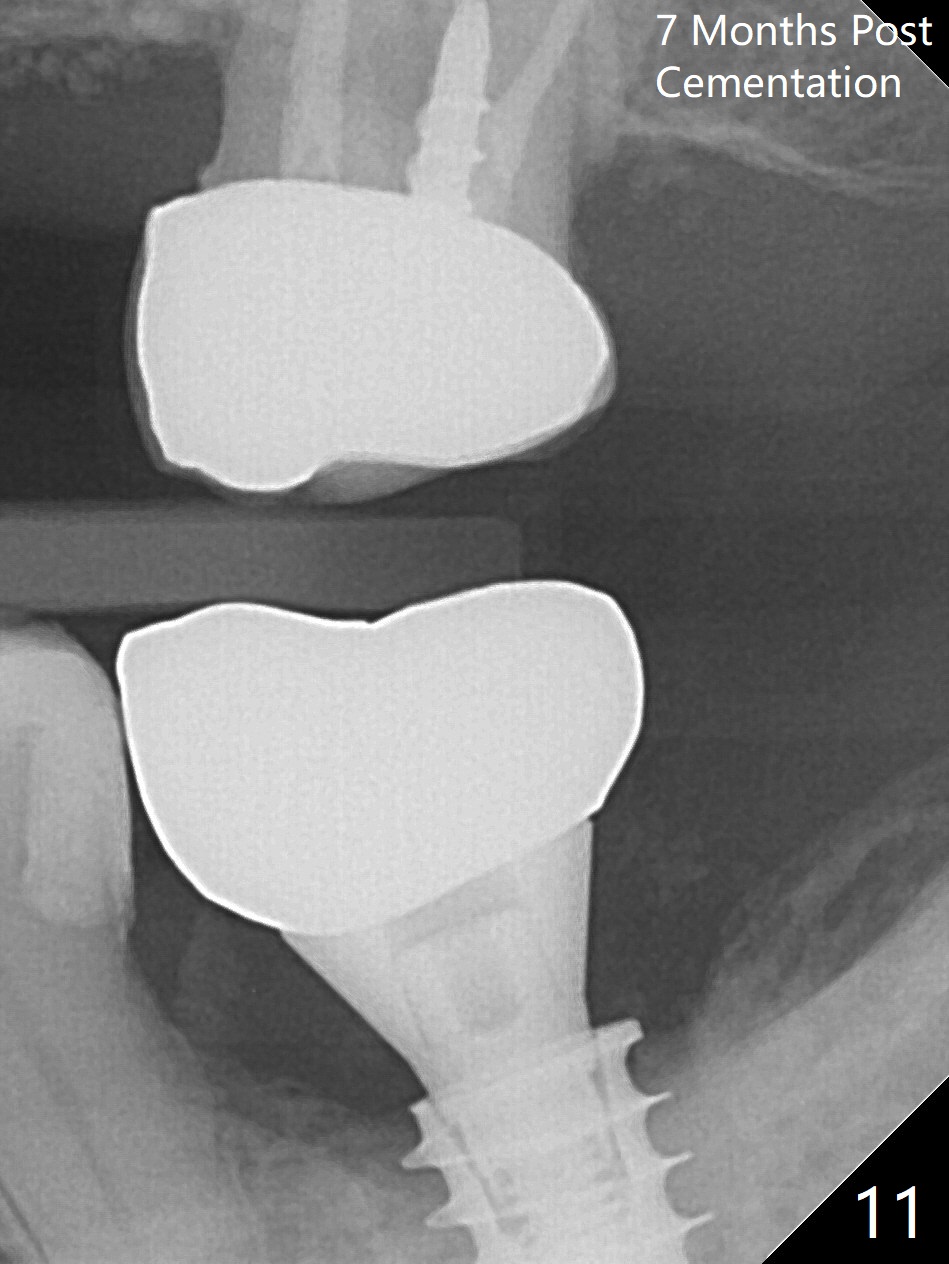

There is no apparent bone loss 4 months postop (Fig.10). There is chewing pain in spite of occlusal adjustment 7 months post cementation (Fig.11-13: increased radiolucency around the implant). The crown/abutment is removed and a healing abutment is placed (6x3 mm); the implant is stable. The patient return for re-evaluation in 3 months (15 months postop); radiolucency appears to reduce (Fig.14). But there is pain when the healing abutment is being removed. After local anesthesia, the implant is removed with a wrench. Following debridement of the osteototomy (intact, although tender), a 5x10 mm dummy implant with SLA surface is placed (Fig.15). After 5.5 mm tap, a 5.5x8.5 mm implant is placed with >50 Ncm (Fig.16). A 6.8x5 mm healing abutment is placed, followed by periodontal dressing. Re-analysis of preop CBCT shows that the bone density at the site is low: 70 units average. Progressive loading is necessary for this case 4-6 months postop. The soft and hard tissues around the implant seem to heal 4 months postop (Fig.17).